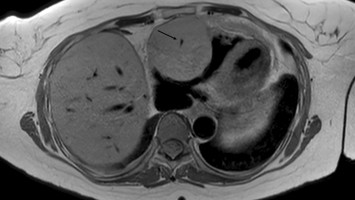

Bei diesem Herztumor war schnelles Handeln nötig

Bildnachweise